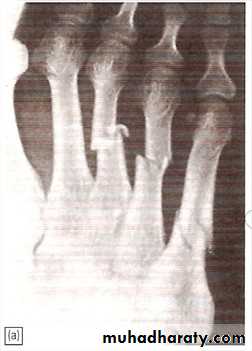

Stress injury (march fracture)

Young adult (often recruit or a nurse)Painful foot after overuse.

Tender lump in shaft of metatarsal (usually 2nd).

X-ray: at first normal but later show hairline fracture and callus.

Radioisotope shows early increased activity.